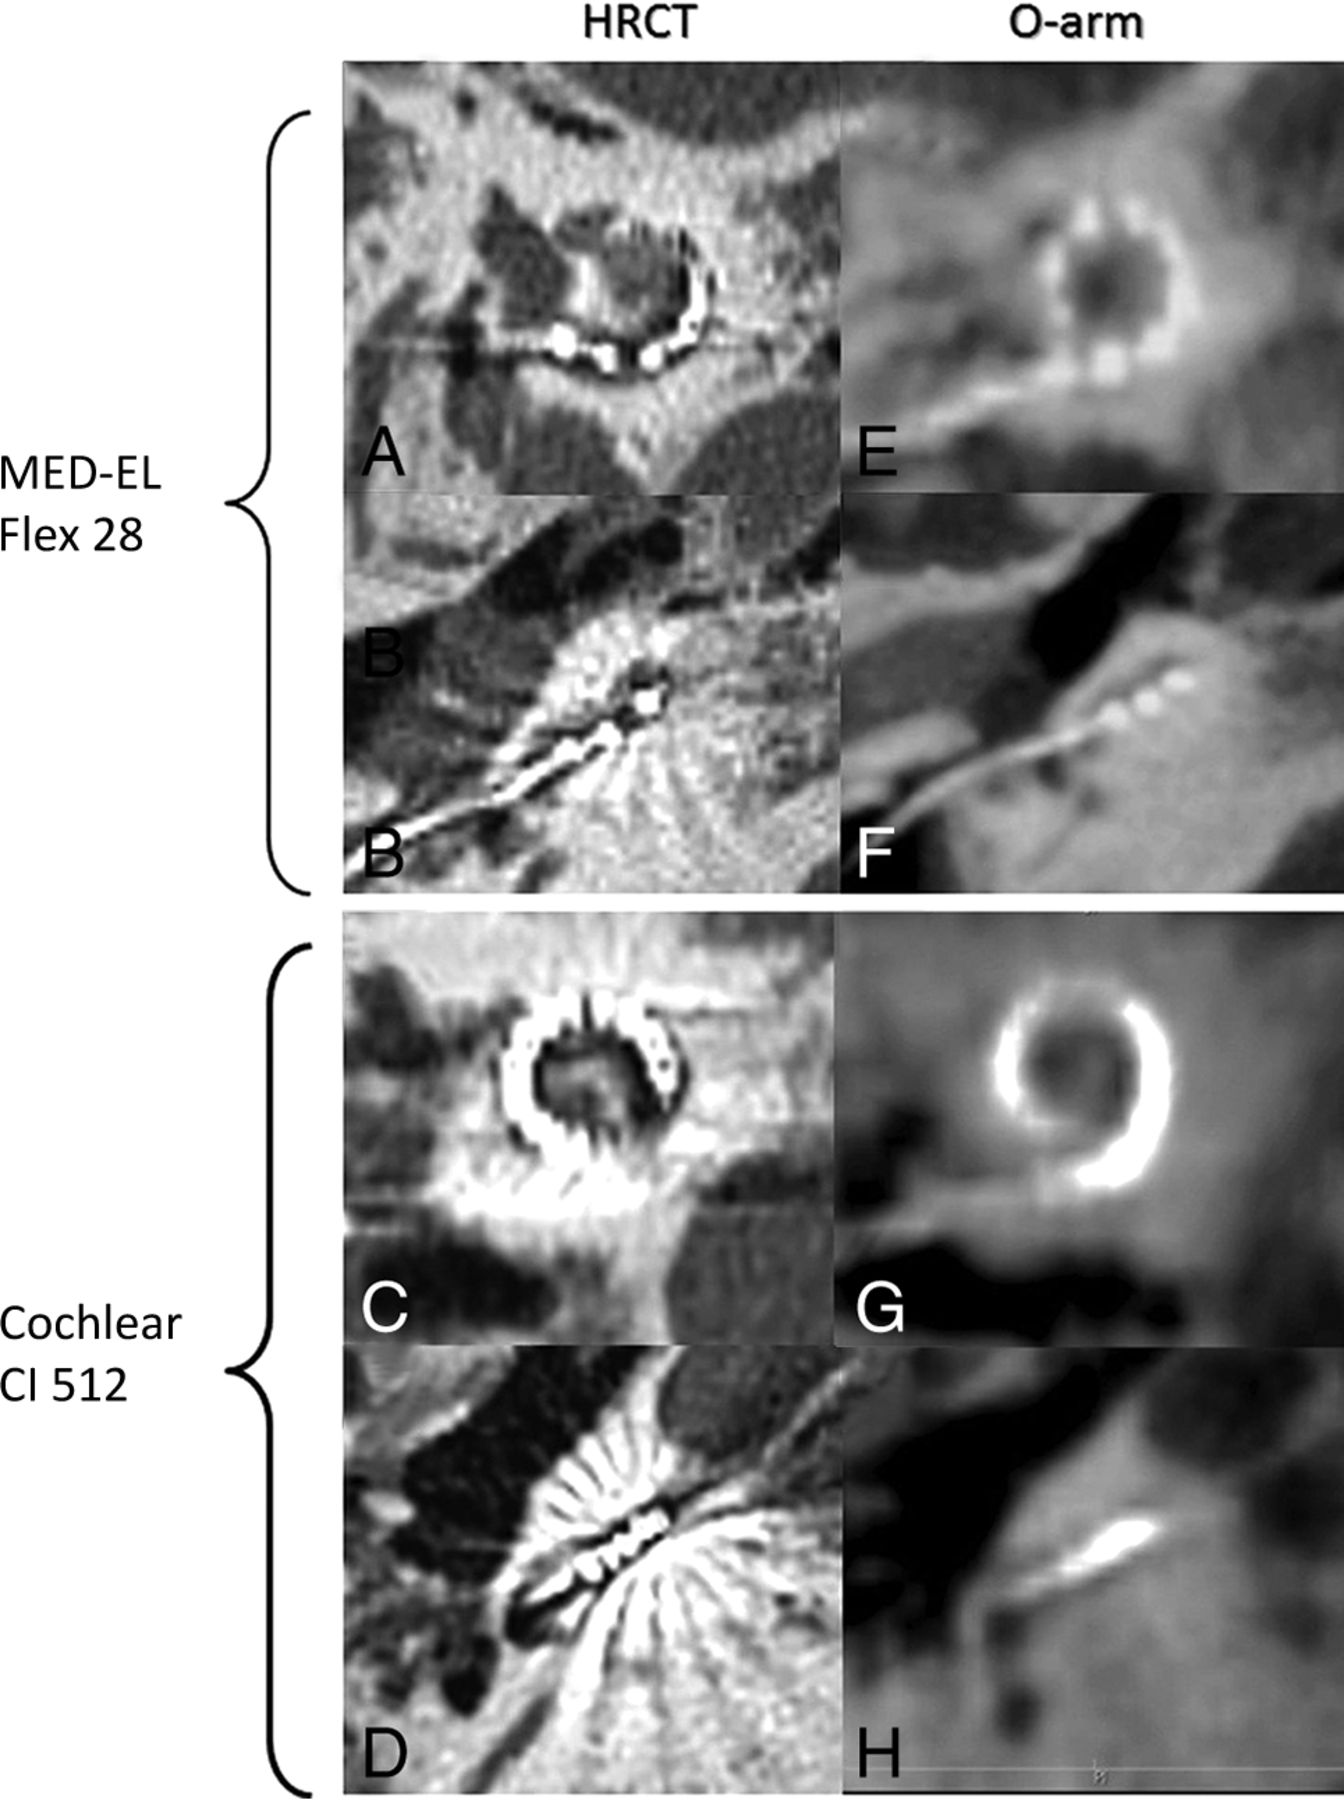

Because the intracochlear electrodes were not clearly shown on O-arm images (Fig 2G, -H), apart from those of the MED-EL implant, which has only 12 electrodes (Fig 2E, -F), the extracochlear electrodes that were more clearly identified were counted. Their numbers were assessed identically between the 2 raters in 50 ears (78%, Cohen κ = 0.53, P < .001), and the identical rates among the different types of arrays did not show a statistically significant difference (Table 4). Regarding the scalar position of the electrodes, initial assessment was the same between raters in only 34/64 ears (53%) at 180° and 20/46 ears (43%) at 360°, with no significant consistency between the evaluations of the 2 raters (Cohen κ = 0.16, P = .10 at 180°; and Cohen κ = 0.14, P = .05 at 360°). After coassessment by the 2 raters, no significant difference was found for the various types of arrays, for the rate of extracochlear electrodes, or for the scalar position (Table 5).

Examples of radiologic images of HRCT and the O-arm for 2 types of cochlear implants. MED-EL Flex 28 (A, B, E, F) and Cochlear CI 512 (C, D, G, H) electrode arrays were observed with both HRCT (A–D) and the O-arm (E–H), and with sagittal (A, C, E, G) and axial (B, D, F, H) views.

With advanced software for DICOM such as OsiriX, which has been approved as a reliable and rapid method for assessing radiologic imaging,16 a more detailed positioning assessment of the electrode array can be realized in the operating room and can give timely feedback to the surgeon. In this series, the insertion depth angle and the length of insertion of the electrode array were assessed promptly (∼3–4 minutes) and showed excellent agreement between the raters' independent assessments. These results also showed excellent agreement with those based on HRCT images, which is the most common imaging procedure and is considered the criterion standard postoperative protocol for the evaluation of electrode arrays in adults. For electrode counting, there was also good agreement between raters, even though it was difficult to clearly distinguish the electrodes near the round window or cochleostomy on O-arm images, especially for arrays with a high number of electrodes (Fig 2); however, the accuracy of electrode counting by the O-arm was still acceptable compared with HRCT. Consequently, O-arm imaging can be considered a reliable tool for assessing the electrode array position in the cochlea in current practice.